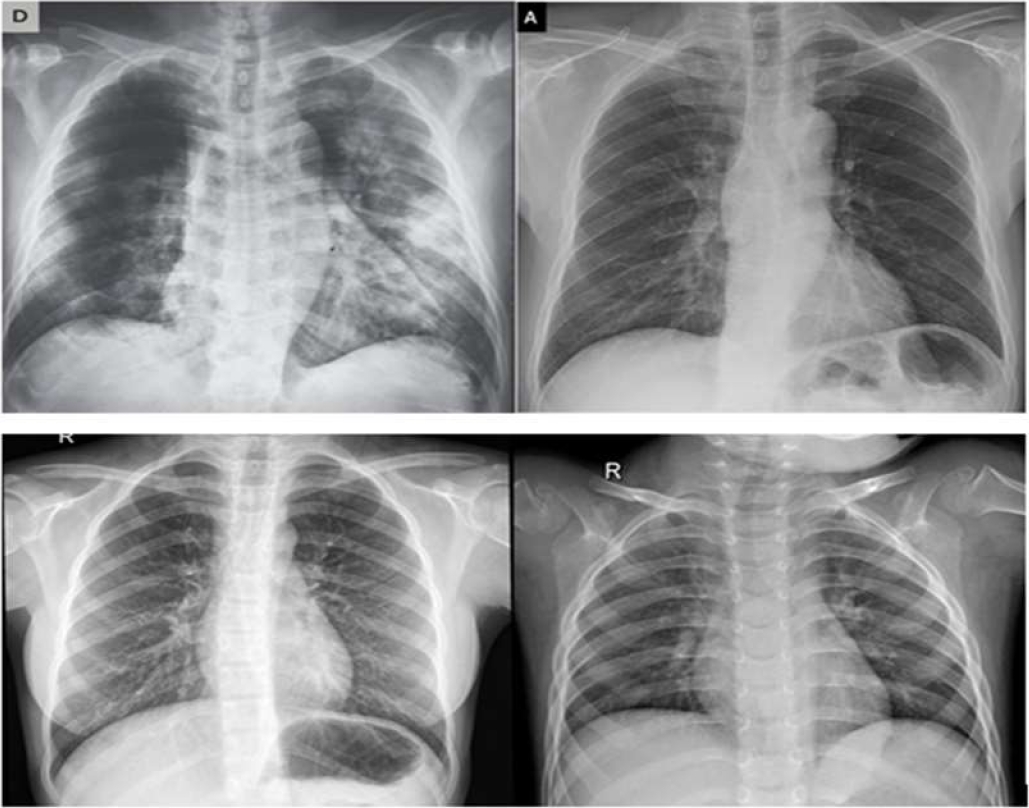

The data is composed of 50 images of chest X-rays and it is divided into two categories: 25 images of healthy people and the rest are those who have Covid19 [5], [6].

The images used in this work are illustrated in Fig. 6.

The figure shows the images used for experimentation. The first row is a normal image and the second row shows a Covid 19 image.